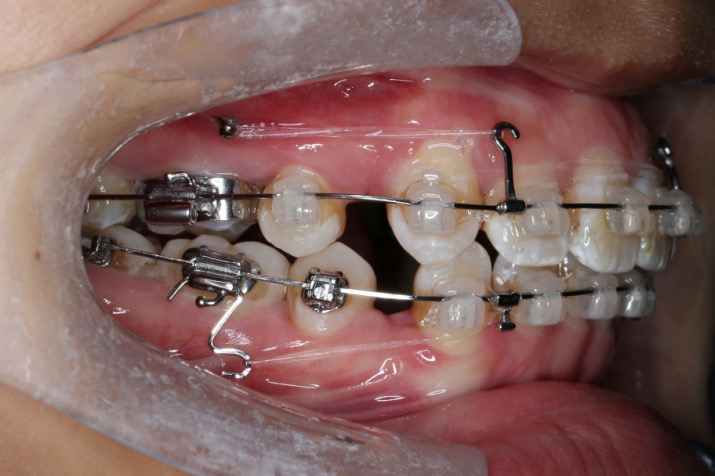

2017.05.26  磨牙近中倾斜,下颌36、46加power arm

2017.07.25

2017.07.25  上前牙加颈部弹力线

2017.10.07

2017.10.07  继续关间隙,下颌使用水平关间隙

下颌磨牙通过powerarm直立效果明显,下颌整平效果明显